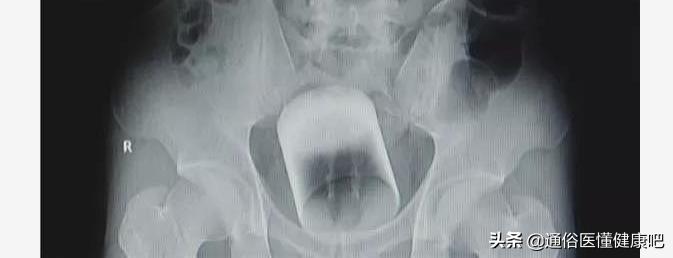

膀胱异物:耳机线